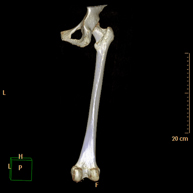

- TC Huesos largos

Exploración radiológica que mediante un sistema de rayos X y detectores que giran alrededor del paciente, reconstruyendo las imágenes por ordenador (TC Multidetector), permite el estudio de huesos largos (tibia, peroné, fémur, húmero, radio y cúbito).